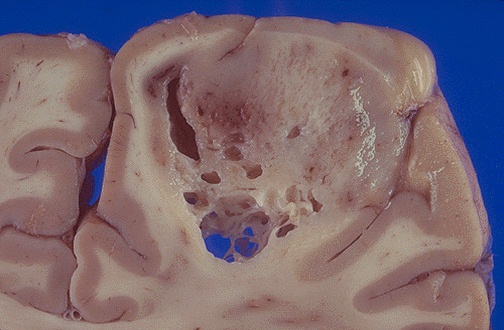

This glioma is arising in the cerebral hemisphere. As in most gliomas, it is difficult to tell where the margin is. [Image contributed by Jeannette J. Townsend, MD, University of Utah]